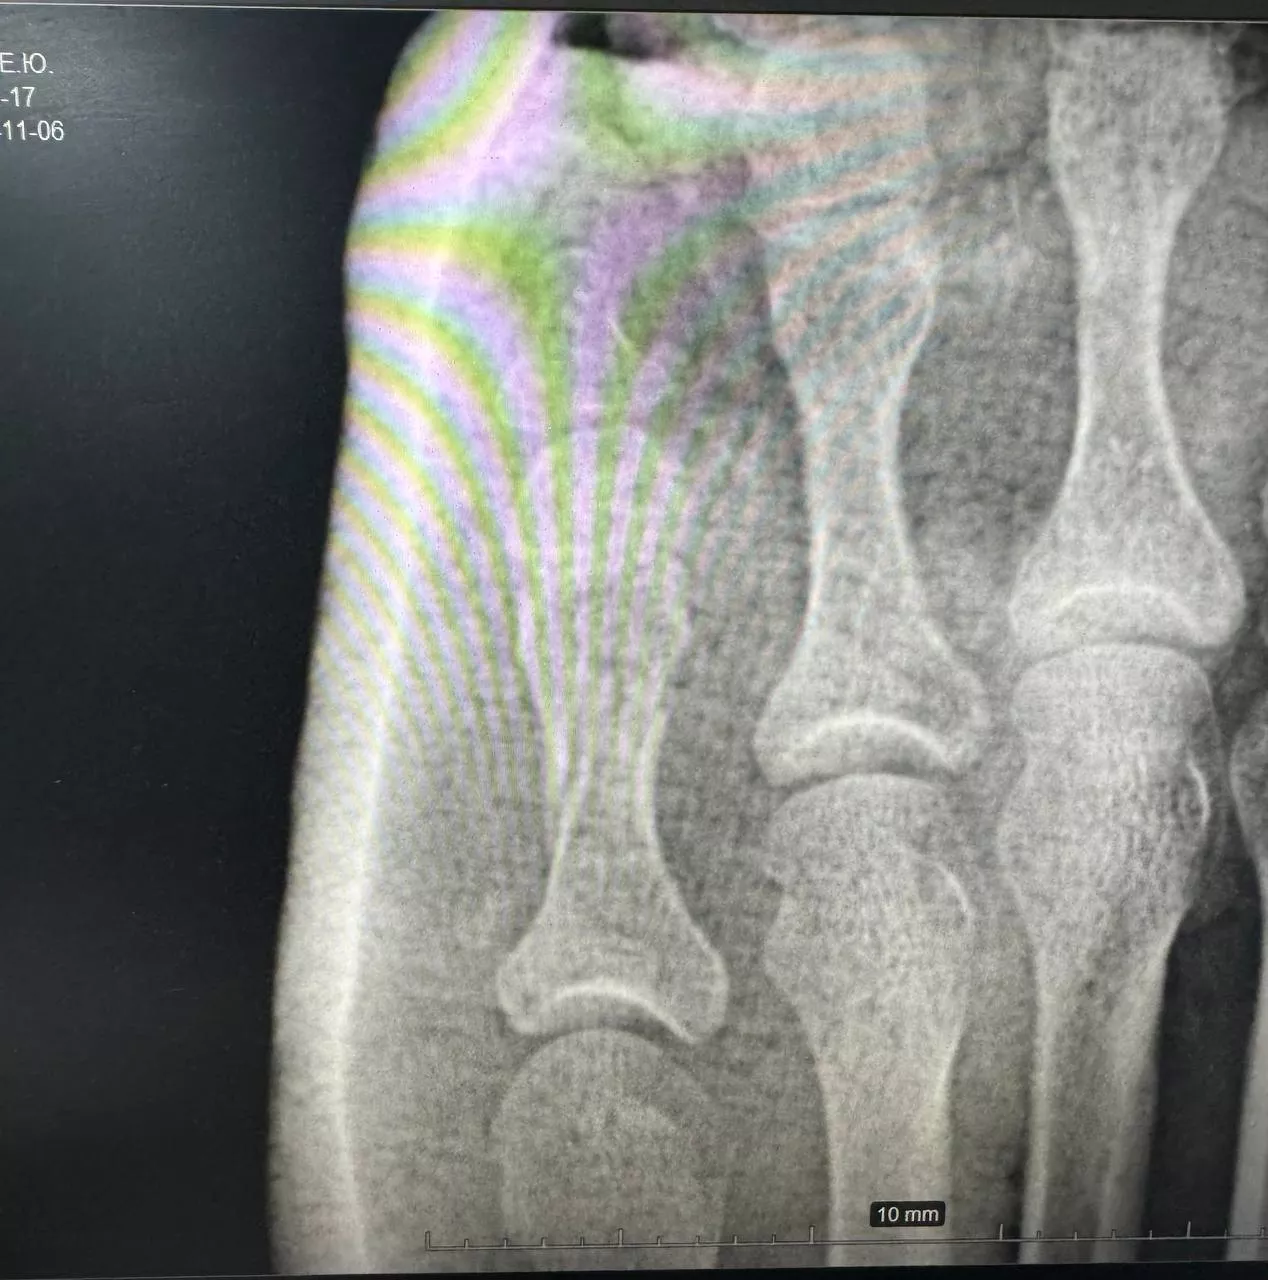

Осмотр и рентгенография позволили поставить диагноз — оскольчатый перелом проксимальной фаланги 5-го пальца. Иван Александрович выполнил репозицию (сопоставление) отломков кости и иммобилизацию стопы гипсовой лангетой. Контрольная рентгенограмма после процедуры позволила оценить результат и убедиться в восстановлении фрагментов. Пациентка довольная уехала домой.

Перелом пятого пальца левой стопы (1) и после репозиции кости и иммобилизации гипсовой лангетой